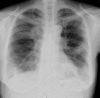

Chondrosarcomas are the most frequently occurring primary malignant chest wall tumors. Furthermore, the lungs serve as the most frequent sites for metastases. Pulmonary metastases from sarcomas usually appear as round nodules of varying sizes on roentgenograms. Here, we report an unusual clinical and radiographic presentation of pulmonary metastasis from a costal chondrosarcoma. Bilateral pulmonary metastases developed soon after wide surgical resection. Thoracic computed tomography revealed unusual radiological findings: consolidation accompanied with ground-glass opacity. To confirm the metastasis, we recommend a transbronchial biopsy in cases where unusual pulmonary findings are detected.